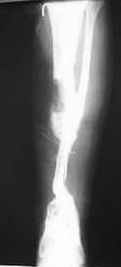

Re: bone defect

Dear Dr. Firas

You can do it like this also...